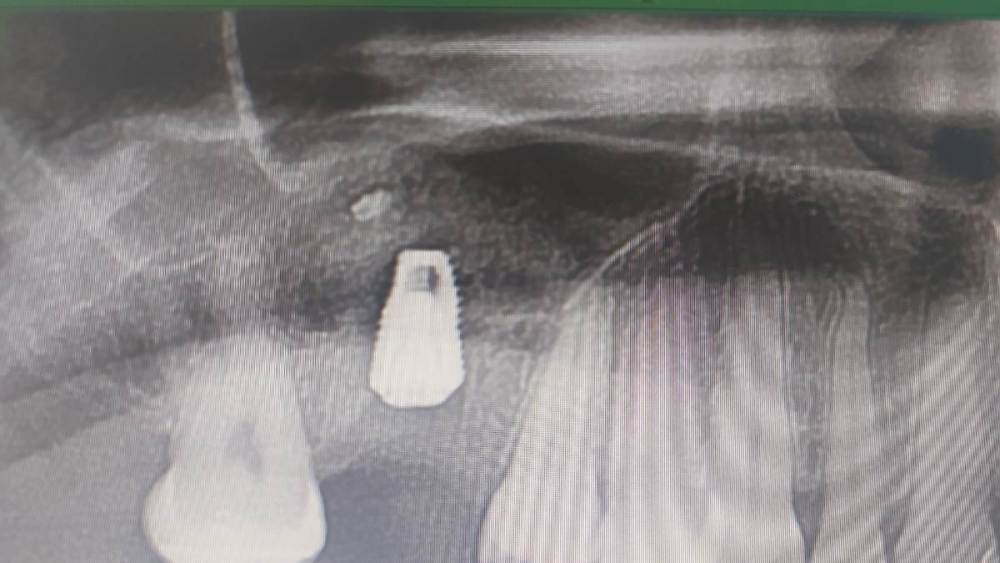

kramer Опубликовано 18 февраля, 2024 Поделиться Опубликовано 18 февраля, 2024 (изменено) Вот на днях делал синус-лифт. Все норм, перфорация была, починил искусственной мембраной Изменено 18 февраля, 2024 пользователем kramer 3 Ссылка на комментарий